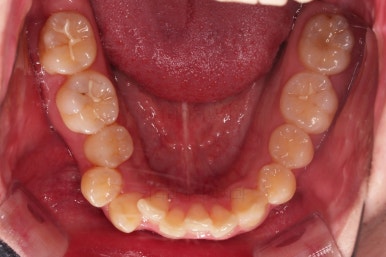

부산교정치과 초진 시 입안의 모습입니다.

앞니가 삐뚤어서 결손치아가 없었더라도 교정치료를 원하셨던 상황이었고요.

오른쪽 어금니 맞물림은 결손치아도 그렇지만 전반적인 앞뒤 차이가 있는 부정교합이 있었어요.

이번 환자분은 부정교합 부분은 발치 없이 치열을 통째로 뒤로 밀어서 개선하기로 했고요.

결손치아 부위는 더 뒤의 어금니와 사랑니까지 앞으로 당겨와서 임플란트 없이 공간을 모아주기로 했어요.